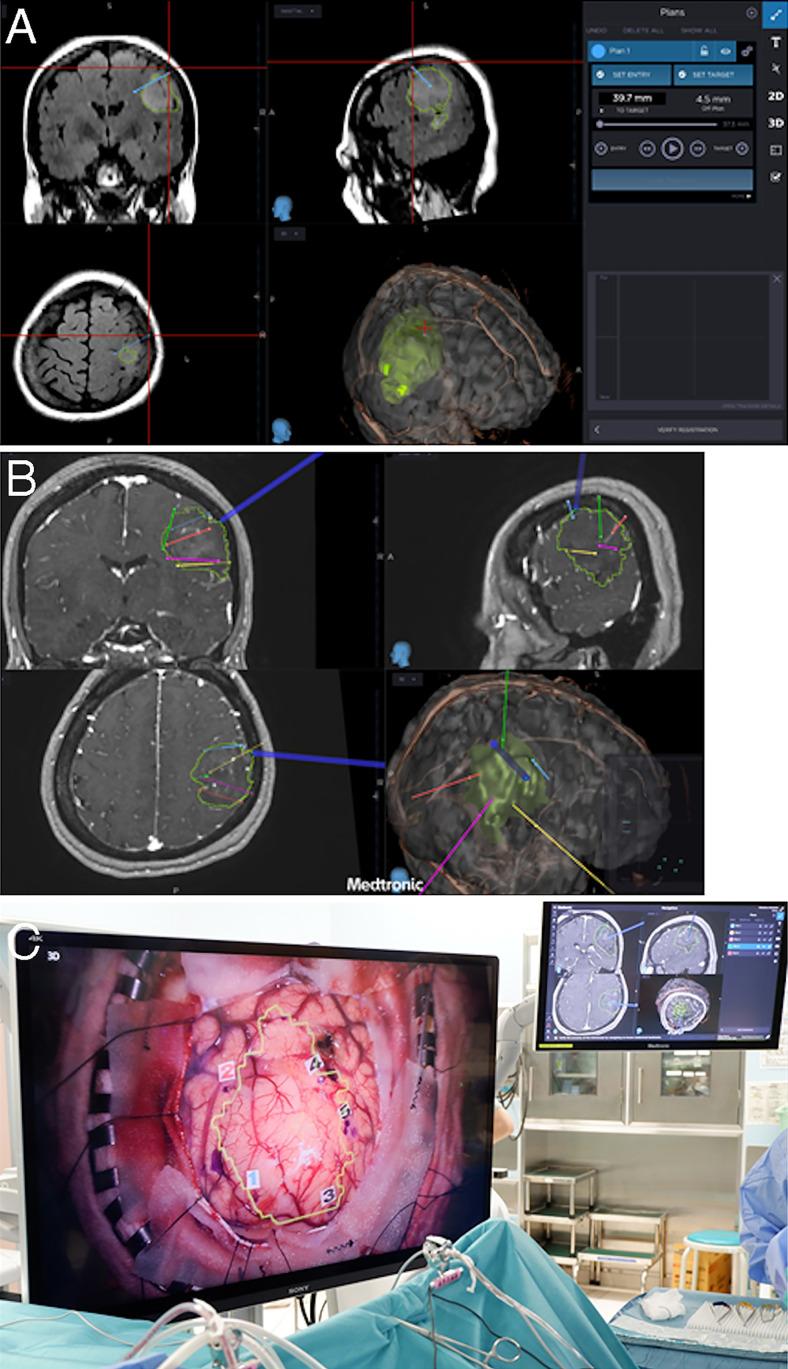

Surgery was performed using the StealthStation S8 linked to the Stealth Autoguide cranial robotic guidance platform and a high-resolution three-dimensional (3D) surgical microscope. A surgical plan was created to determine the removal area using fence-post tube placement at the tumor and normal brain tissue boundary. Using this surgical plan, the robotic system allowed quick and accurate fence-post tube positioning, automatic alignment of the needle insertion and measurement positions in the brain, and quick and accurate puncture needle insertion into the brain tumor. Use of a ventricular drainage tube for the outer needle cylinder allowed placement of the puncture needle in a single operation. Furthermore, use of a high-resolution 3D exoscope allowed the surgeon to simultaneously view the surgical field image and the navigation screen with minimal line-of-sight movement, which improved operative safety. The position memory function of the 3D exoscope allowed easy switching between the exoscope and the microscope and optimal field of view adjustment.

观察结果

手术使用与Stealth Autoguide颅骨机器人引导平台相连的StealthStation S8和高分辨率三维(3D)手术显微镜进行。制定手术计划,通过在肿瘤与正常脑组织边界处放置栅栏式导管来确定切除区域。利用该手术计划,机器人系统能够快速准确地进行栅栏式导管定位,自动对齐脑内针插入和测量位置,并将穿刺针快速准确地插入脑肿瘤。使用脑室引流管作为外针筒可在单次手术中放置穿刺针。此外,使用高分辨率3D外视镜可使外科医生以最小的视线移动同时查看手术视野图像和导航屏幕,从而提高了手术安全性。3D外视镜的位置记忆功能便于在外视镜和显微镜之间轻松切换并进行最佳视野调整。